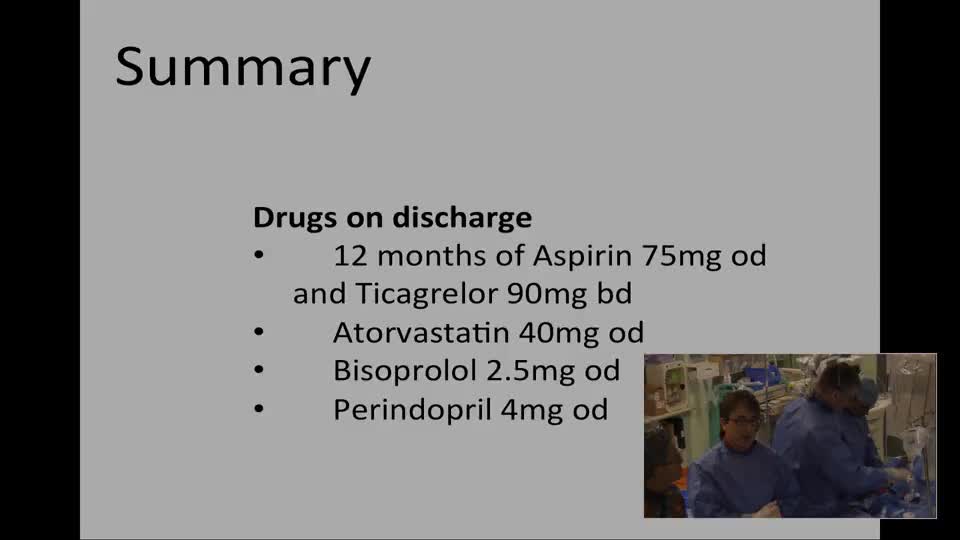

What Medication Should the Patient Have on Discharge and Why? - Dr. Ricardo Pertraco